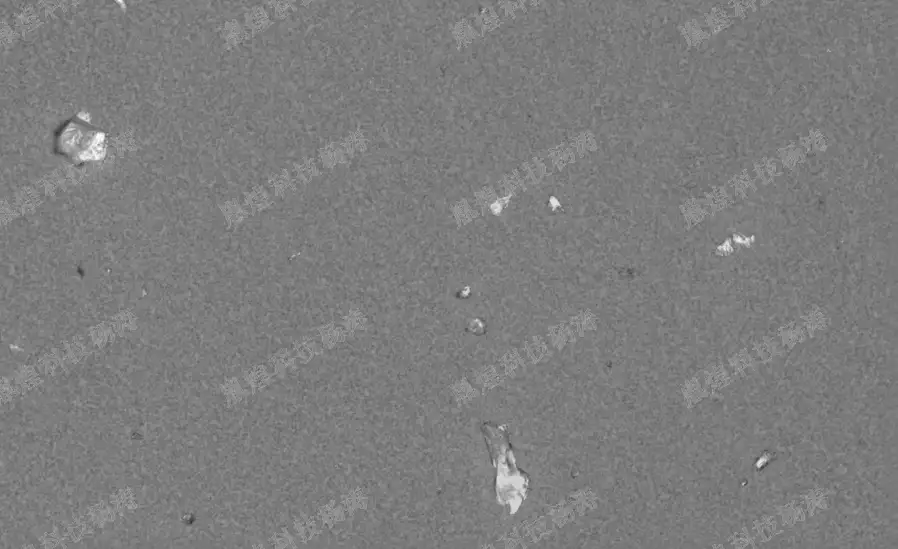

下图为胤煌科技设备拍摄的一些玻璃微粒的图片: